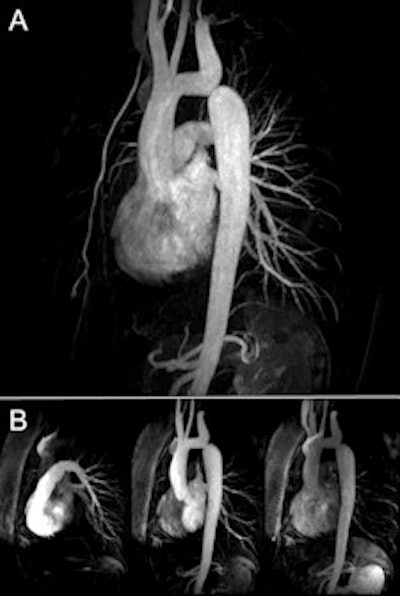

A: Single-dose (0.1 mmol/kg body weight) high-resolution (0.8 x 0.8 x 0.8 mm3) MR angiography in coarctation of the aorta (CoA). B: 3-tesla dynamic MR angiography performed at high temporal and spatial resolution. Images courtesy of Dr. Bernd Wintersperger.